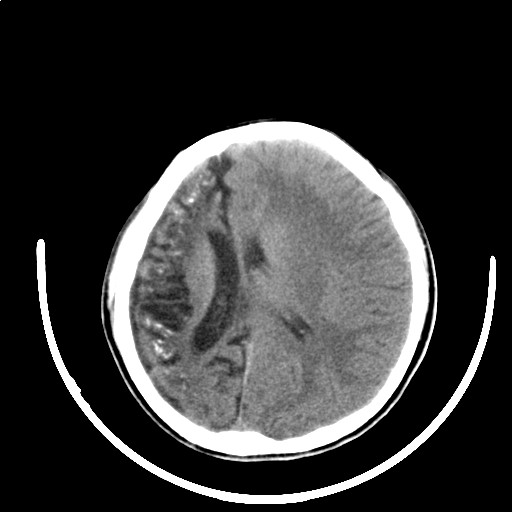

标题: PED3416:F,12Y,智力下降,学习成绩差,8个月时发过高烧。

右侧半球萎缩,软化,多量脑回样钙化,考虑颅面血管瘤病,建议dsa检查

右侧半球萎缩,软化,多量脑回样钙化,同侧颅盖板障增宽,考虑颅面血管瘤病,建议dsa检查与化脓性脑膜炎后遗改变鉴别。